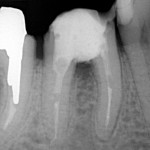

Jeśli przeleczony kanałowo

ząb jest wrażliwy a zdjęcie rentgenowskie wykazuje defekt kostny w obrębie

bifurkacji czyli w miejscu rozdzielenia korzeni, wszystko wskazuje

na to, że dno komory zęba jest zniszczone, a nieszczelnośc ta spowodowała

zniszczenie kości w tym miejscu. Zachowawcze leczenie jest niemożliwe.

Jeśli chce się uratowć taki

ząb, jedynym rozwiązaniem jest separacja czyli premolaryzacja. Zabieg ten

wykonuje się w znieczuleniu miejscowym. Wiertłem przecina się ząb, tak

by odsłonić całą perforację dna komory. Stwarza się w ten sposób dwa oddzielne

zęby. Miejsce przecięcia należy bardzo dokładnie i szczelnie zabezpieczyć

kompozytem. Jest to dość trudne w wilgotnym, podziąsłowym miejscu. Jeśli

leczenie kanałowe jest nieszczelne należy je wykonać ponownie.